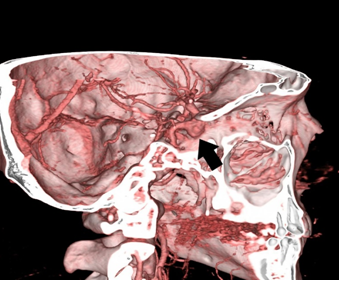

Computed tomography (CT) angiography and magnetic resonance imaging (MRI) were performed, revealing the presence of two aneurysms: a wide-necked aneurysm in the cavernous segment of the right internal carotid artery (ACI) and a small wide-necked aneurysm in the anterior communicating artery (AcomA) (Figures 1-2).

Figure 1: Saccular aneurysm in the cavernous segment of the right ACI.

Figure 2: Wide-necked saccular aneurysm in the cavernous segment of the right ACI.